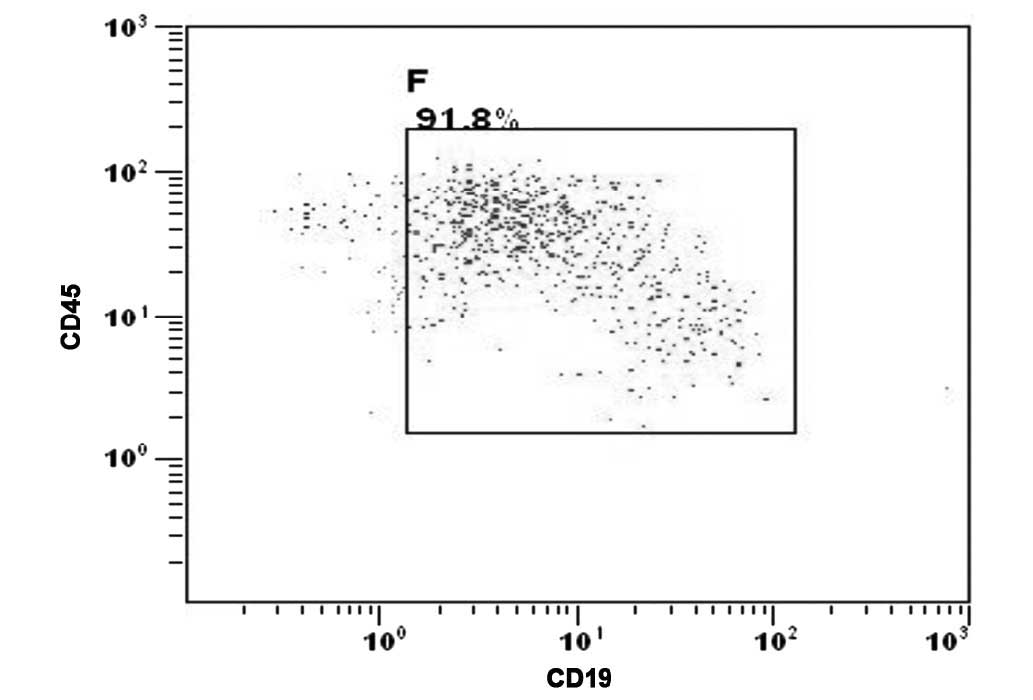

(Fig. 1A). Leukemic infiltration of

the CNS was confirmed by the presence of malignant leukemia cells

detected in the cytospin of the cerebrospinal fluid (CSF) (Fig. 2).